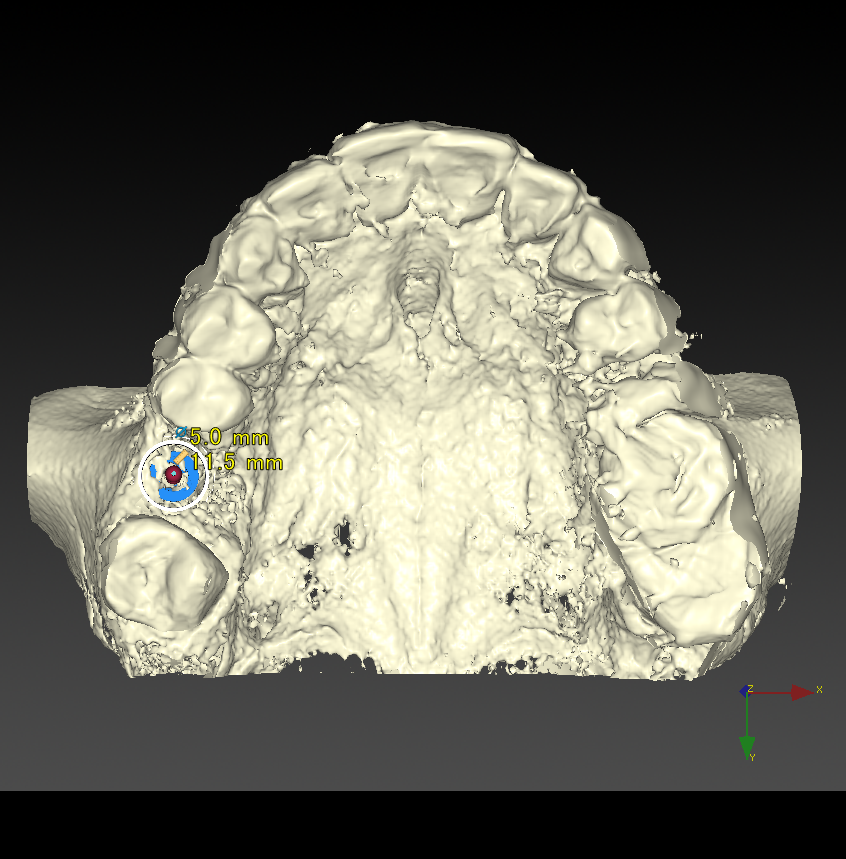

CT撮影

埋入位置を決めるための装置(ラジオグラフィックガイド)を口腔内に入れCTを撮影します。

埋入ガイド

CT画像上にて決定した埋入位置で製作された埋入ガイド。正確でスムーズな手術を行えます。

CTシミュレーション

CTデータをインプラント解析ソフトに入れ、手術のシミュレーションをします。

・骨の状態を確認し、骨造成が必要か見極めます。

・シミュレーションでインプラントが可能か確認し、インプラントのサイズを調べます。